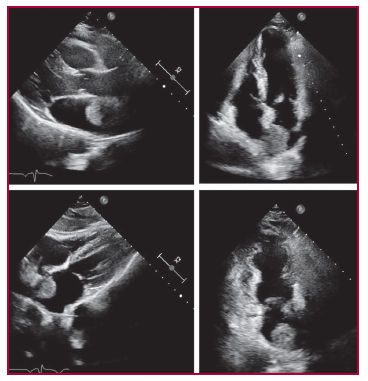

Espondiloartropatía inflamatoria como única manifestación del mixoma auricular izquierdo